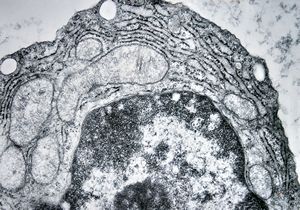

M,43y. | skin - susp. myelosis

M,43y. | skin - susp. myelosis … Auer bodies

M,43y. | Auer bodies - myeloid leukemia v.s.

M,43y. | blood - susp. myeloid leukemia -Auer bodies